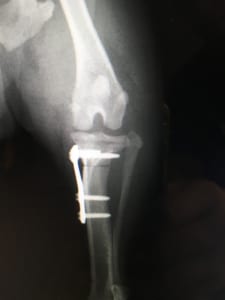

↑ 梨の木どうぶつ病院で実施されたTPLOの術後画像。